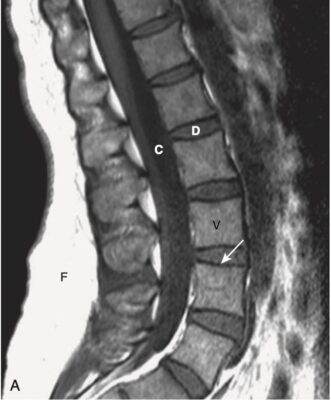

- Trên hình ảnh MRI cột sống đứng dọc T1W, các thân đốt sống, chứa tủy xương, thông thường sẽ có cường độ tín hiệu cao (sáng), các đĩa đệm sẽ có cường độ tín hiệu thấp hơn và dịch não tủy (CSF ) trong túi cùng sẽ có cường độ tín hiệu thấp (tối) (Hình 4, A).

- Trên hình ảnh T2W thông thường, thân đốt sống sẽ có cường độ tín hiệu thấp hơn một chút so với đĩa đệm, trong khi dịch não tủy sẽ sáng (ngược lại của T1) (xem Hình 4, B).

- Xương vỏ có tín hiệu thấp (tối) trên tất cả các chuỗi xung.

- Sự giảm hàm lượng nước trong nhân nhầy dẫn đến cường độ tín hiệu của đĩa thấp hơn trên hình ảnh T2W (xem Hình 6).